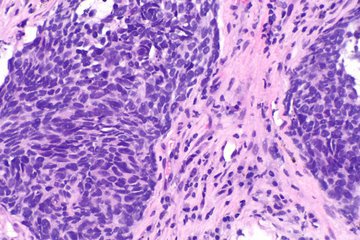

В рамках передачи «Жить здорово!» телеведущая Елена Малышева рассказала, как мужчины могут проверить наличие рака яичек. Для этого необходимо провести простой тест на беременность.